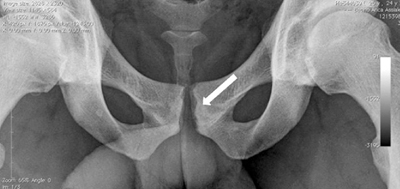

Рентген костей таза

Обычно данная процедура применяется после родов для диагностики разрыва симфиза, а затем для мониторинга процесса восстановления. В период беременности рентгенпельвиометрия, то есть измерение размеров таза, осуществляется реже. Это состояние позволяет дополнительно оценить соответствие размеров таза и головки плода.

Для диагностики данного состояния и определения его степени применяется ультразвуковое исследование. Кроме того, во время пальпации врач может заметить, что хрящ стал мягким, а тазовые кости проявляют нестабильность.